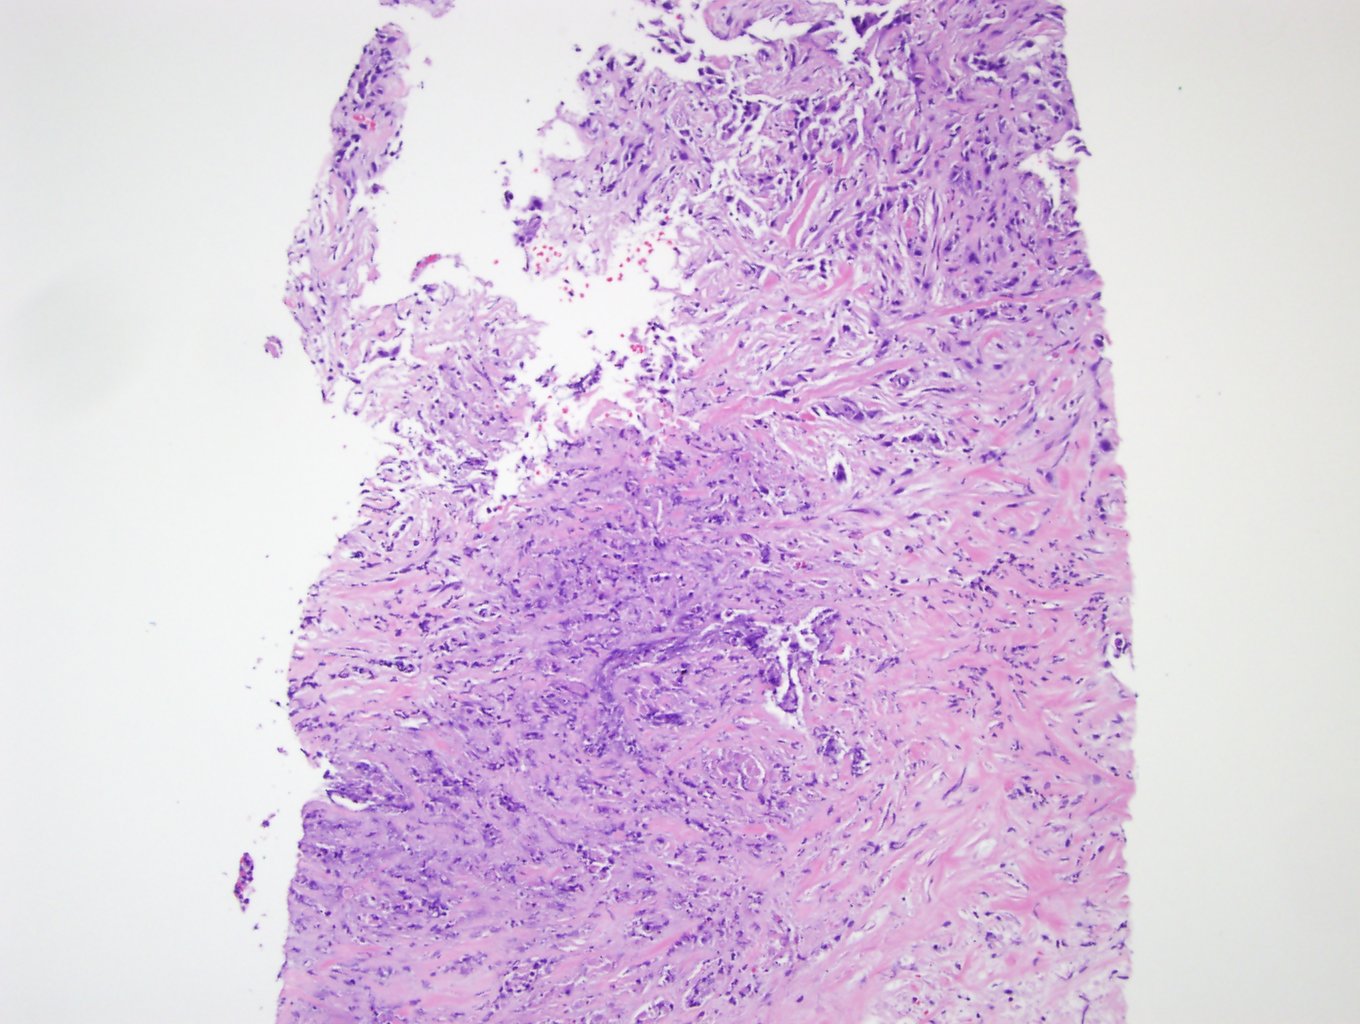

The patient underwent biopsy of the right neck mass (Figures 1-4). The tumor is relatively undifferentiated with scattered tumor cells in a dense desmoplastic stromal background, although there are areas where the malignant cells are cohesive, supporting a diagnosis of carcinoma. Overall, the tumor cells are pleomorphic, with hyperchromatic nuclei and irregular nuclear contours. No normal structures such as thyroid or lymph node are identified histologically. Immunostaining of the tumor demonstrated positive staining for cytokeratin 7, PAX8 (Figure 5), and p63; the tumor cells did not stain with cytokeratin 20, thyroglobulin (Figure 6), TTF-1, BRST-2, or estrogen receptor.